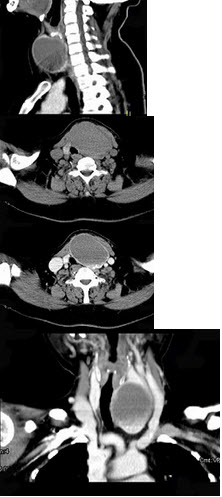

女,56岁,发现颈部肿块30天,颈部肿大,无红肿热痛,无呼吸困难,无吞咽困难,无心悸胸闷烦躁史。近1个月来因肿大不适而来就诊。发病来饮食睡眠正常,体重无下降。如图所示该患者最可能诊断为( )

A:甲状舌管囊肿

B:甲状腺乳头状癌

C:甲状腺原发淋巴瘤

D:甲状腺腺瘤

E:甲状腺脓肿